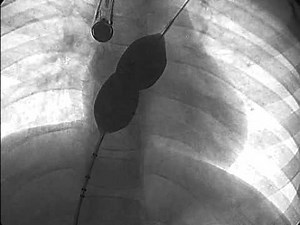

- Amplatzer Device

VSD - Amplatzer Device

Amplatzer Device - Amplatzer

PDA - Amplatzer

ASD - Amplatzer

Septal Occluder - AVP Closure

Piccolo Occluder - Amplatzer

Duct Occluder - PDA Heart Coil